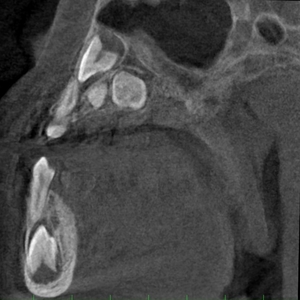

パントモCT装置

使用装置:モリタ社製ベラビューX800

2021年7月に歯科口腔外科系の撮影を行うパントモCT装置が新たに導入されました。

この装置では、2次元的に歯や顎の撮影を行うオルソパントモ撮影や顎関節撮影に加え、3次元で立体的に歯や病変を描出できるコーンビームCT撮影の機能も搭載されました。そのため従来の装置と比較して、より画質の良い、診断に有用な優れた画像検査が可能となります。

| 任意断面画像(横断像) | 任意断面画像(冠状断) | 任意断面画像(矢状断) |